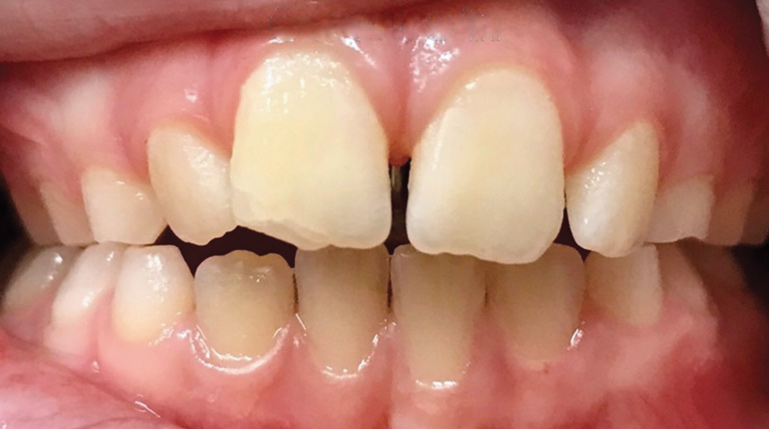

Fig 9. Anteroposterior view of class II (Fig 9) and class III (Fig 10) malocclusion. Arrows indicate positions of the mesial maxillary cusp and embrasure between the mandibular molar cusps. In class II malocclusion the maxillary molar is more anteriorly positioned, while in class III the mandibular molar is more anteriorly positioned.

Figure 9

Fig 10. Anteroposterior view of class II (Fig 9) and class III (Fig 10) malocclusion. Arrows indicate positions of the mesial maxillary cusp and embrasure between the mandibular molar cusps. In class II malocclusion the maxillary molar is more anteriorly positioned, while in class III the mandibular molar is more anteriorly positioned.

Figure 10

Class II malocclusions (Figure 9) may be treated to reduce risk of dental trauma of protruding maxillary incisors or to break a lip trap habit. Some devices used for this purpose include headgears or functional appliances. Many orthodontists may wait to treat class II malocclusions in the permanent dentition because studies find inconclusive evidence of the effectiveness of phase I treatment.28 Early intervention is a strong consideration for class III malocclusion (Figure 10), with the goal of avoiding surgical treatment for either an adolescent or adult. This approach takes into consideration psychological-social concerns as well with regard to balancing facial disproportions and correcting the appearance of an "underbite" and/or prominent lower jaw.29 However, because there is a genetic component, surgery cannot be ruled out as a comprehensive treatment option. An early intervention would include facemask therapy with RPE to orthopedically protract and widen the upper jaw.